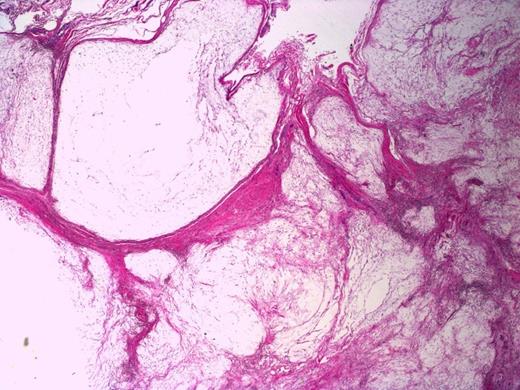

Involvement of a tendon (lower right corner) by the myxoma. Note bluish dense extracellular mucin in the right upper corner. H&E stain, 40X magnification

Sections of the lesion showed dense fibrous tissue with nodules of extracellular myxoid material containing scattered histiocytes and stellate to spindled fibroblastic cells. There was no evidence of necrosis, atypia or malignancy; this was consistent with Juxta-articular myxoma. (Figure 4 and 5). At one year follow-up there has been no sign of recurrence.